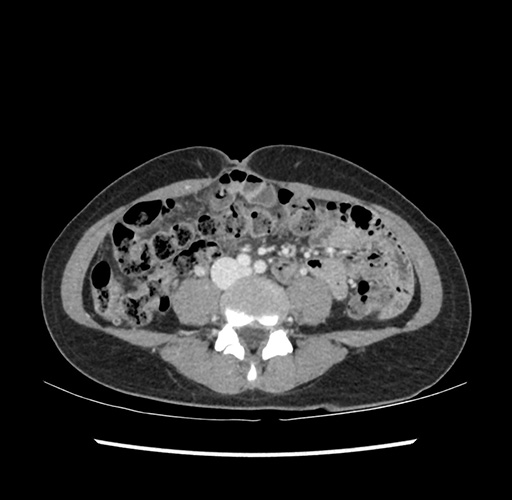

Imaging Analysis

Look through the patient's CT scan to identify any areas of concern for the necessary procedure.

Based on your CT findings, which issue(s) would give reason for "planned slowing down moment(s)" in this case?